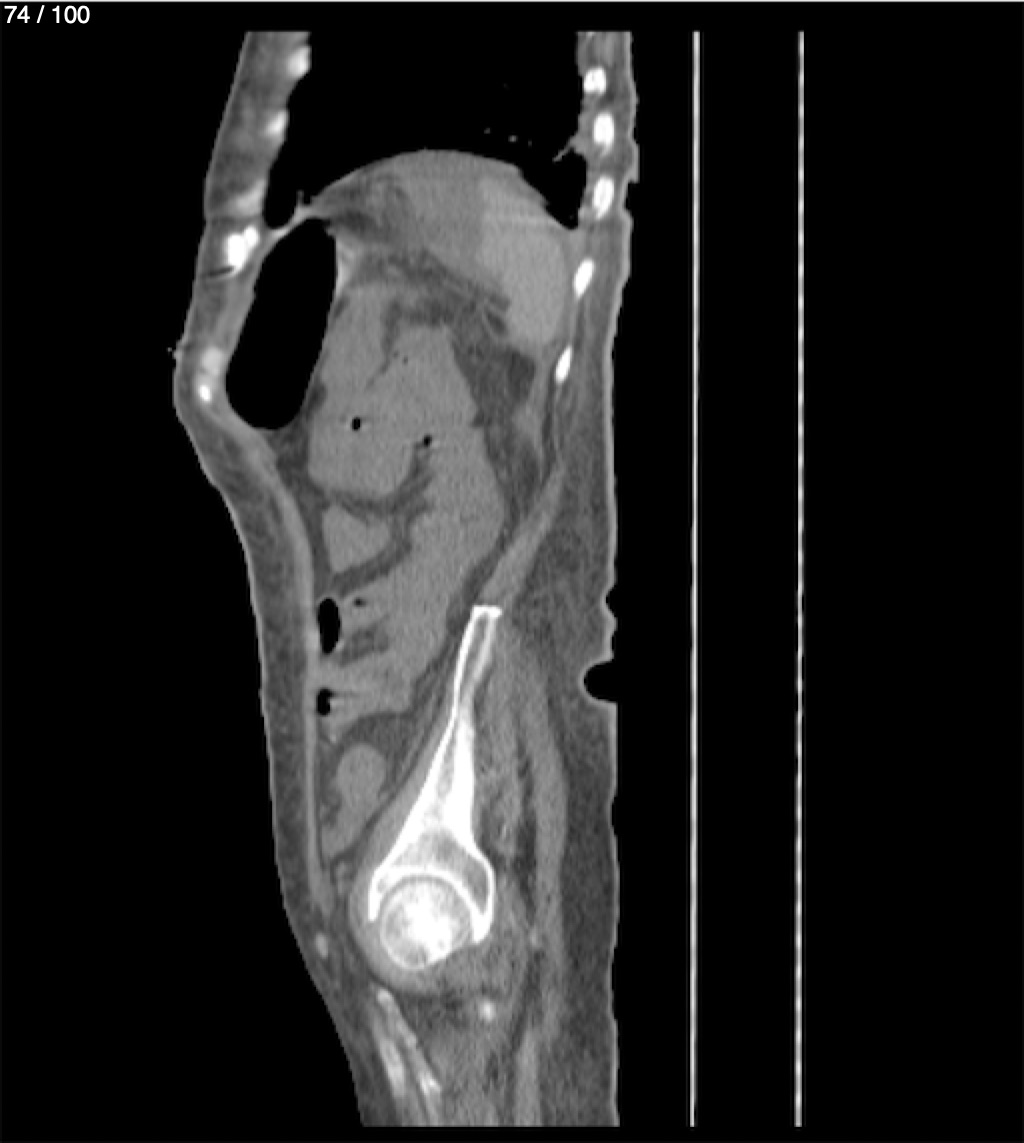

Hilda Geronimo Mendez 60A - T.C Abdomen Simple